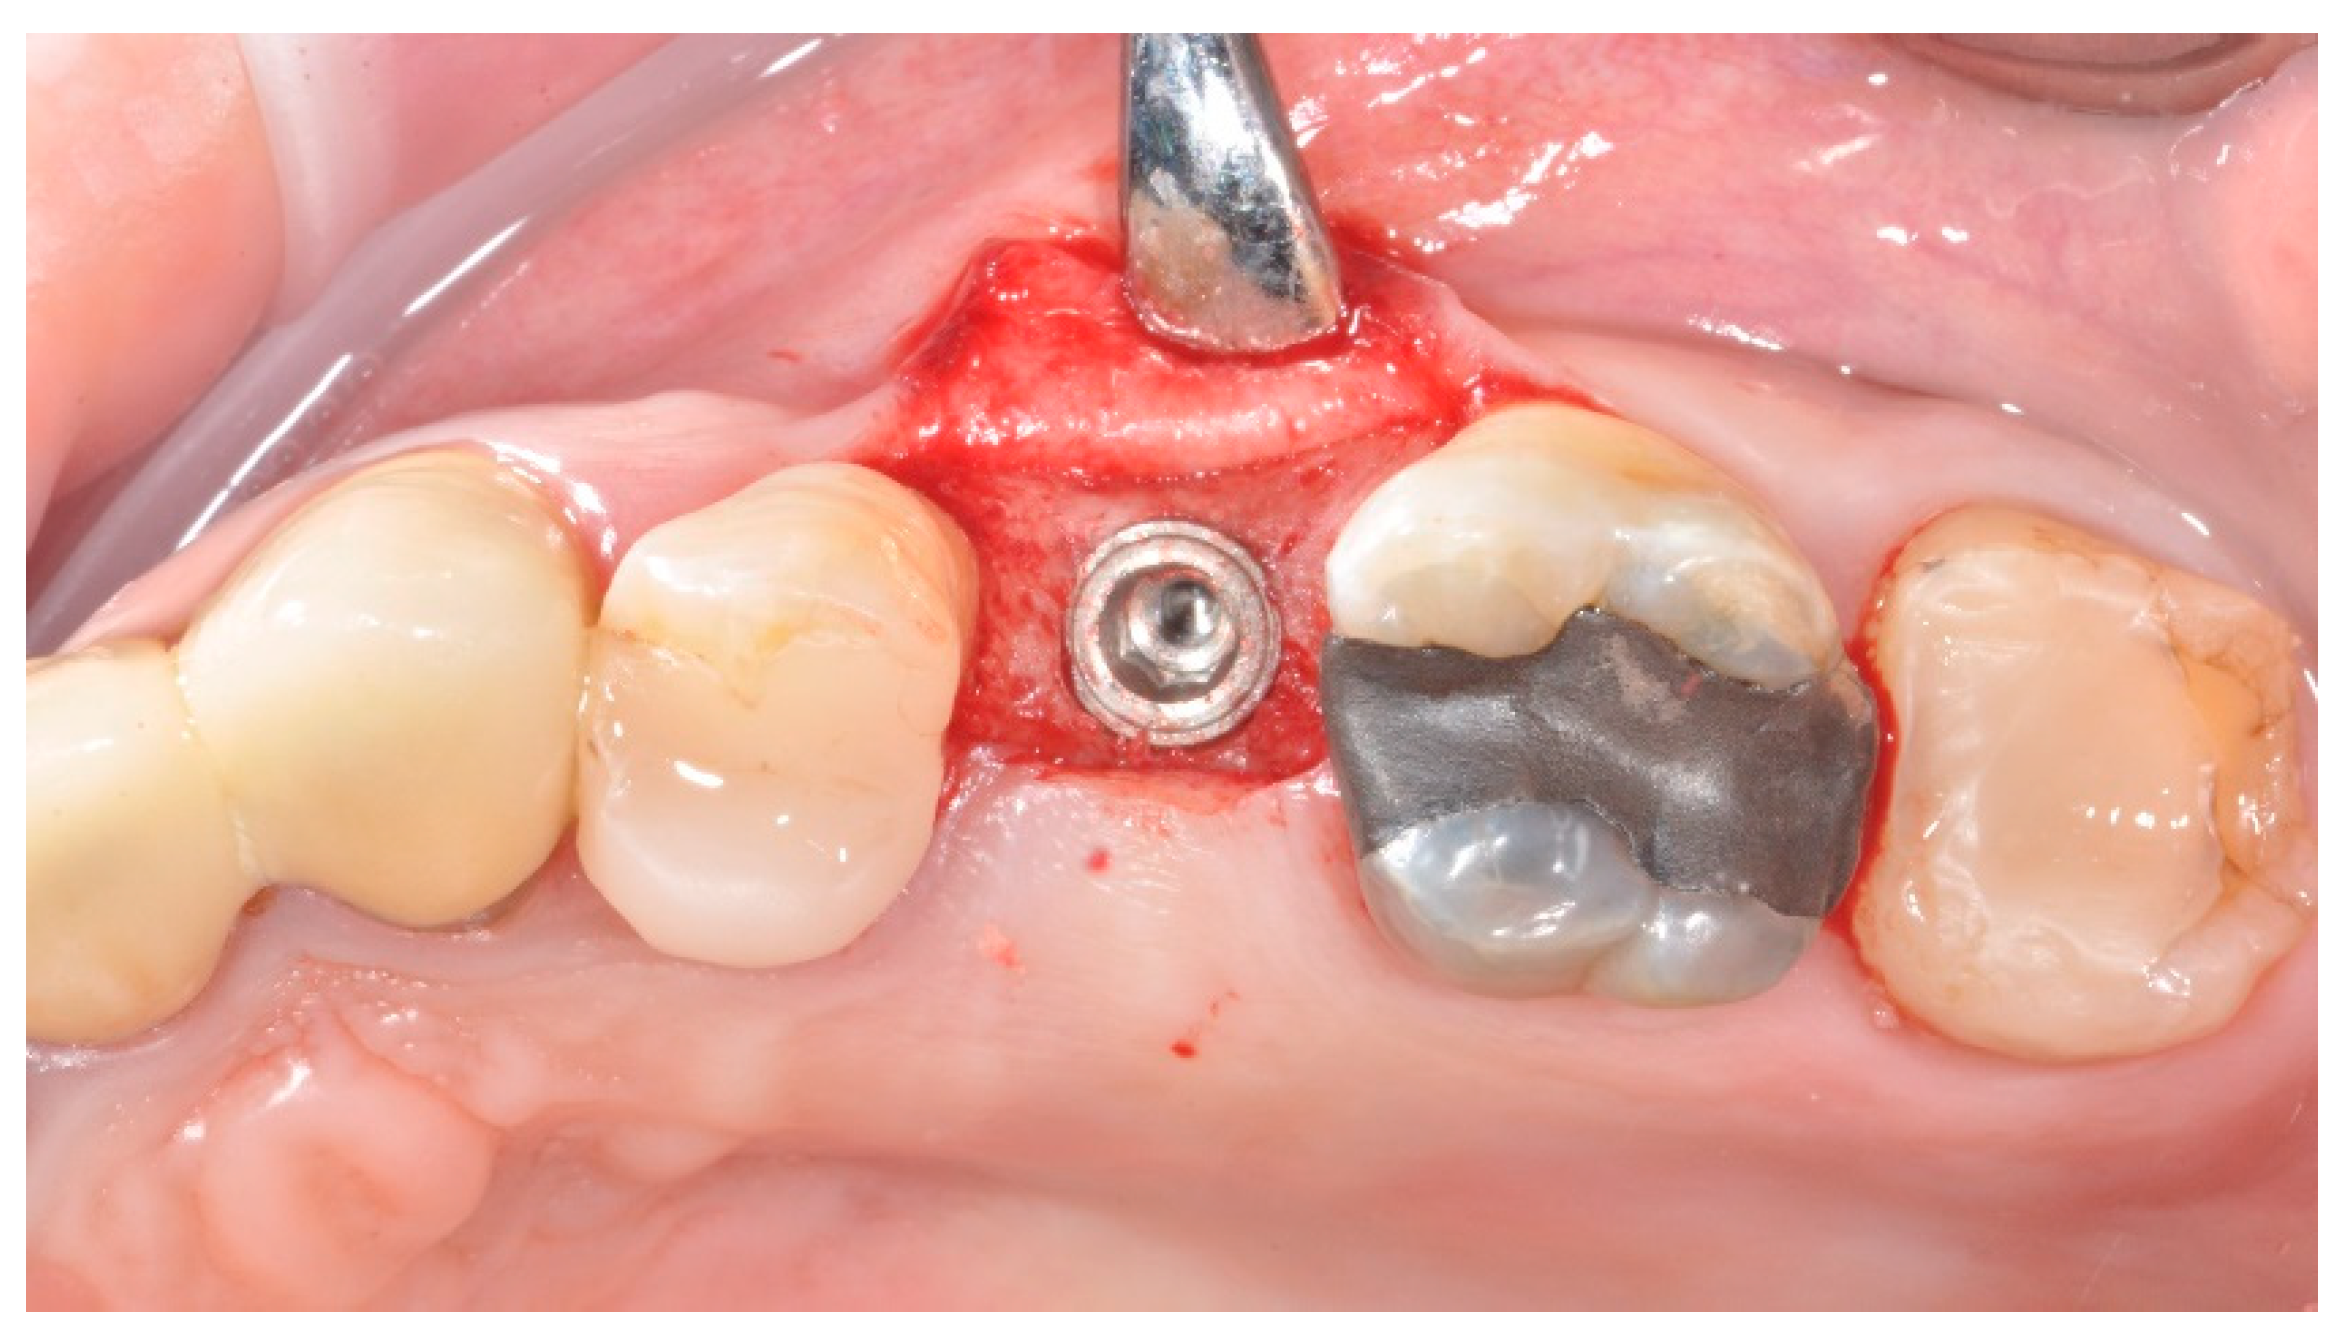

2.2. Surgical Procedures

2.3. Prosthetic Protocol